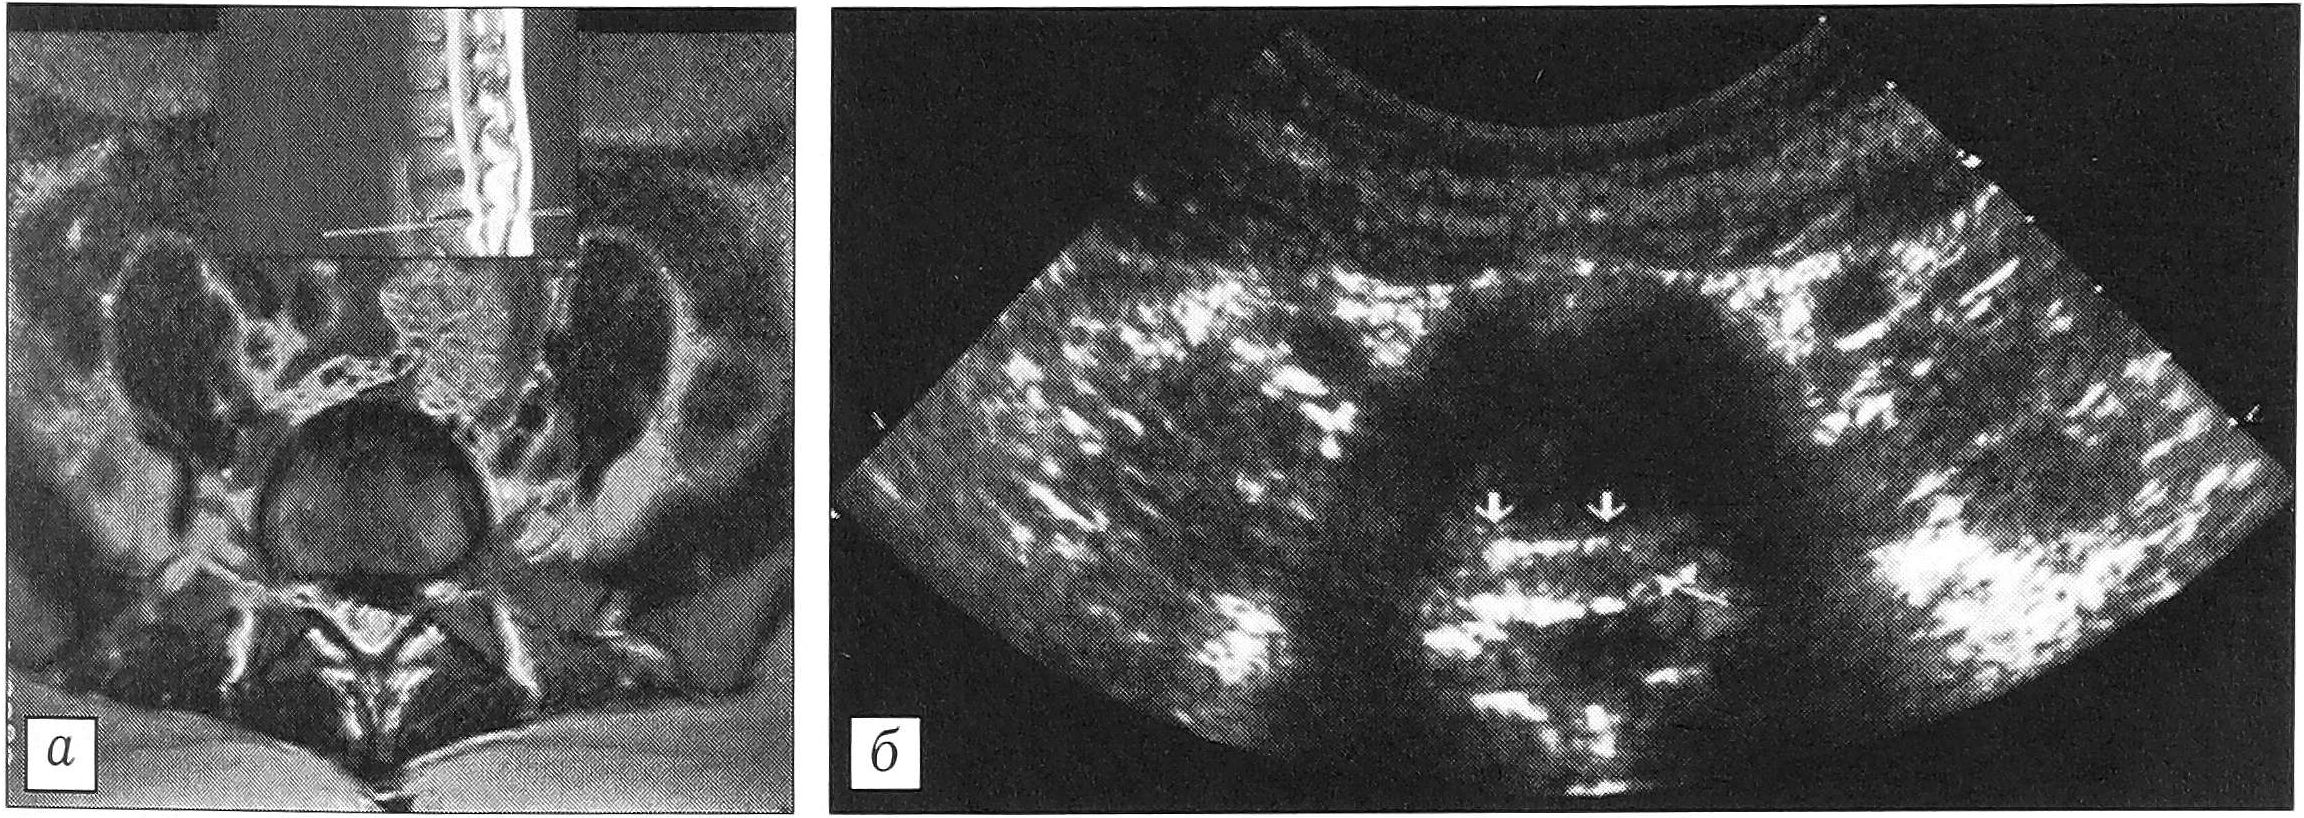

Фиброзное кольцо с четким контуром, без дополнительных эхо-сигналов в толще выявлено в 57 межпозвонковых дисках. На появление дистрофических изменений указывали уплотнение его внутреннего контура, слоистость. В 13 дисках отмечены утолщение или двухконтурность фиброзного кольца. Согласно исследованиям А.Ю. Кин- зерского [6], это свидетельствует о нестабильности в данном сегменте. В 18 случаях фиброзное кольцо было деформировано при сохранении его структуры, что обусловливалось смещением пульпозного ядра с образованием протрузии (рис. 1). Истончение и разрыв фиброзного кольца (локальные гиперэхогенные сигналы в его толще) свидетельствовали о наличии грыжи. Последняя выявлена в 6 случаях: в одном —центральная, в трех —- парамедианная (рис. 2) и в одном — заднебоковая.

Рис. 1. Протрузия межпозвонкового диска. а — МРТ в аксиальной проекции; б — ультрасонограмма той же больной: определяется расширение границ фиброзного кольца.

Рис. 2. Грыжа диска. а — МРТ в аксиальной проекции; б — ультрасонограмма того же больного: определяется разрыв фиброзного кольца.

При выраженной протрузии и грыже диска уменьшаются переднезадние размеры позвоночного канала, возникает его деформация и асимметрия корешковых рукавов (7 случаев). У одного и того же пациента в поясничном отделе позвоночника выявлялись неизмененные и поврежденные диски.